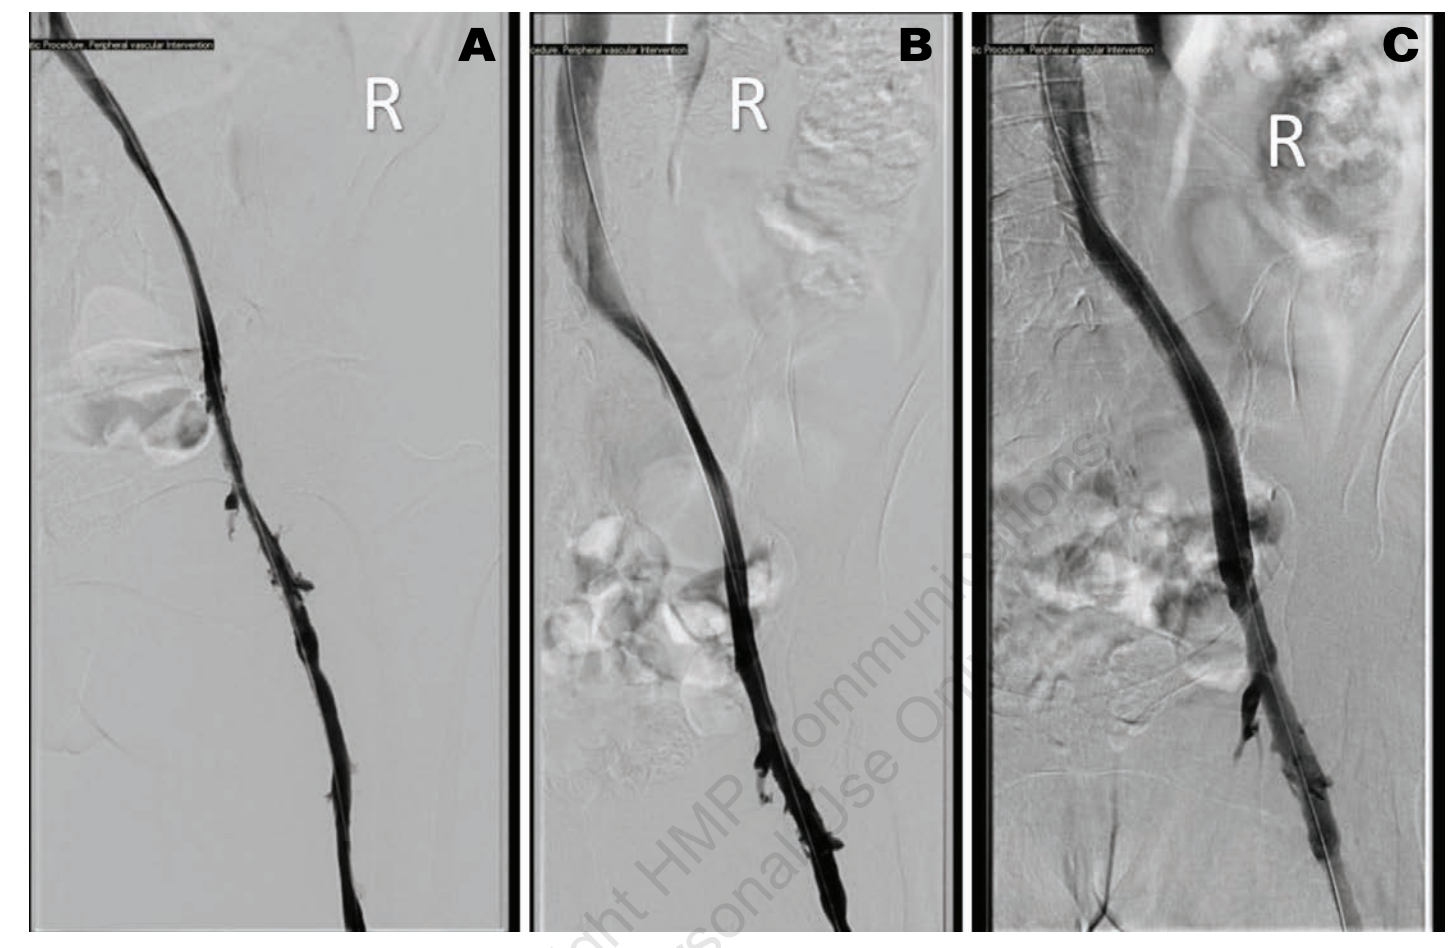

A 57-year-old woman with a history of severe rheumatoid arthritis and urothelial carcinoma of the bladder with a chronic urostomy in place was referred to our clinic for chronic right lower extremity pain and swelling. At the time of original presentation, she was experiencing symptoms for 2 years. Our initial workup with venous duplex US of the lower extremity showed patent veins with no evidence of thrombus; severe venous reflux disease was noted in the right greater saphenous vein (GSV) and small saphenous vein (SSV). After failed conservative management for several months with a graded compression stocking, leg elevation, and calf exercises, she underwent ablation of the GSV with Varithena (Boston Scientific), followed by ablation of the SSV a few months later with radiofrequency ablation. Despite ablation, swelling persisted, and 2 months after her vein ablation she presented with dramatically worsened lower extremity pain, swelling, and redness. US of the lower extremity showed occlusive DVT of the right CFV. We scheduled her for a right venogram with planned thrombectomy of the proximal acute DVT. Access was obtained from the right popliteal vein with US guidance. The vein was initially accessed with micropuncture because the popliteal vein caliber was exquisitely small. After access, the micropuncture sheath was upsized to 8 Fr. Contrast was injected through the 8 Fr sheath to obtain diagnostic images. The patient had 90% stenosis of the right CFV with a heavy thrombus burden and severe, diffuse compression of a small caliber right EIV of 70%. An IVUS catheter was advanced into the EIV and pulled back to confirm the degree of stenosis. This confirmed small-caliber central vein sizes. IVC measured 8.3 mm in the minor axis and 16 mm in the major axis, with a cross-sectional area of 112 mm2; EIV measured 7.4 mm in diameter and 65 mm2 in a cross-sectional area; and CFV measured 11 mm in diameter and 103.8 mm2 in a cross-sectional area (Figure 3). The patient underwent thrombectomy of the right CFV utilizing ClotHunter (Boston Scientific) with ZelanteDVT (Boston Scientific), with excellent clot debulking of 0% residual clot burden after thrombectomy. For the EIV, a balloon angioplasty was performed with a 12 x 80 mm Charger balloon (Boston Scientific), which did not result in reduction of the stenosis. A 12 x 140 mm Zilver Vena stent was placed in the common iliac vein to EIV and post-dilated with the same balloon with good results.

No residual stenosis was noted post procedure (Figure 4). At the end of the procedure, hemostasis of the popliteal vein was obtained with manual compression. On follow-up over the next 6 months, the patient’s edema slowly decreased and substantially improved, along with eventually improved pneumatic mechanical compression. Her pain symptoms completely resolved soon after the procedure.